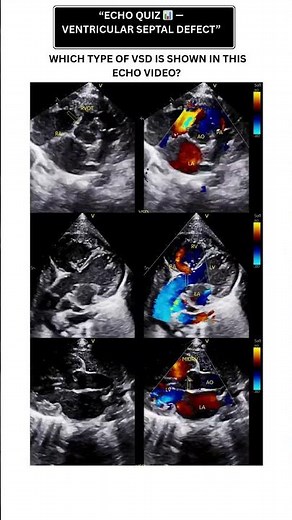

Tee - VSD

VSD Echo